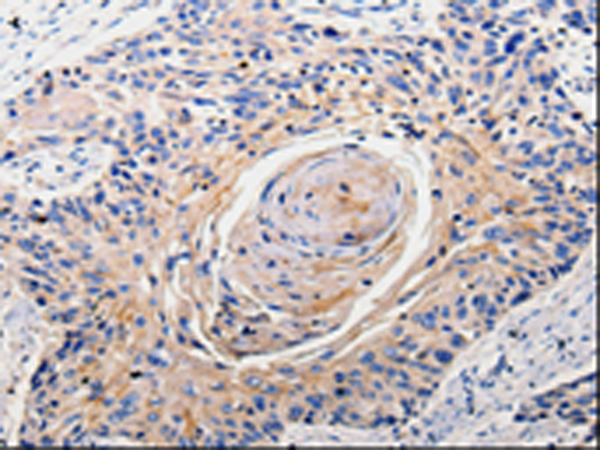

ELISA, WB, IHC

IHC positive control:

IHC Recommend dilution: